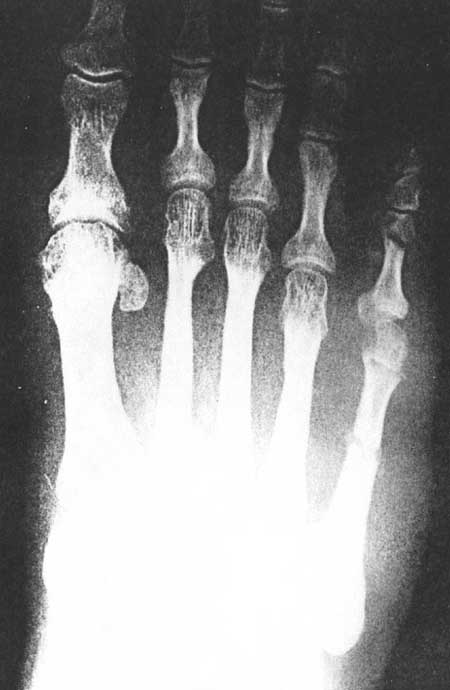

Fig 3B (pre-operative)

|

Fig 3B (post-operative)